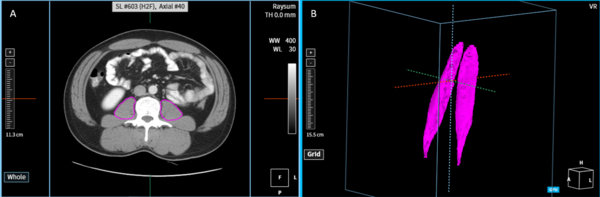

서울아산병원 김지완 교수 연구팀은 코어라인의 AI 솔루션 AVIEW를 활용해 자동으로 요근의 부피를 정확하고 신속하게 진단할 수 있는 방법을 개발했다. 논문명은 ‘Development and validation of a reliable method for automated measurements of psoas muscle volume in CT scans using deep learning-based segmentation: a cross-sectional study’로, 요근의 부피를 정밀하게 측정해 근감소증의 조기 발견 및 치료에 큰 도움을 줄 수 있다.

해당 연구에서는 520명 참가자의 CT 스캔 데이터를 활용해 요근 영역을 자동으로 분할하고 부피를 측정하는 nnU-Net 기반의 인공지능 모델을 개발한 것으로, 코어라인소프트의 AI 솔루션 AVIEW에서 구현됐다. 이 방법은 전문가가 요근 영역을 수동으로 직접 분할하는 것 보다 48배 더 빠르며, 인공지능이 자동으로 추정한 요근모양의 정확성을 의미하는 Dice score도 평균 0.927로 높은 효율성과 정확성이 입증됐다.